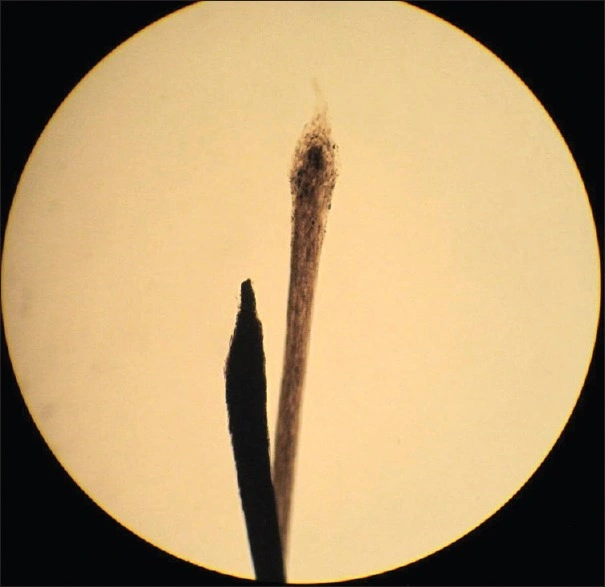

However, once that stops, the hair shaft is narrowed, weakened and damaged. As a result, it breaks and falls off. On being pulled, you can see the dystrophic hair (misshapen bulb and no root sheath) with a pencil-pointed end.

Anagen hair with the pointed distal end to the left and Telogen hair to the right. Occipito-vertical alopecia after radiation exposure. Verma S, Srinivas C, Thomas M. Radiation-induced temporary alopecia after embolization of cerebral aneurysm. Indian J Dermatol. 2014 Nov;59(6):633. doi: 10.4103/0019-5154.143584. PMID: 25484428; PMCID: PMC4248536/CC BY-NC-SA 3.0.

| Hair Appearance | Pencil-point | Club-shaped |